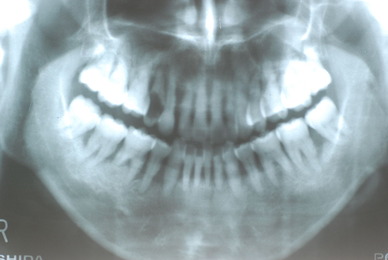

ある方の例です。親不知が痛くなってきました。一見問題ないようです。でも歯周病を常に治療している優れた歯科医師ならば、乾燥させてみた歯茎の色の変化で殆ど歯周病罹患部を指摘できるそうです。

検査をすれば恐ろしいほどの状態だといえるのです。10年後は虫歯と歯周病で残っている歯は何本なのか心配になってきました。